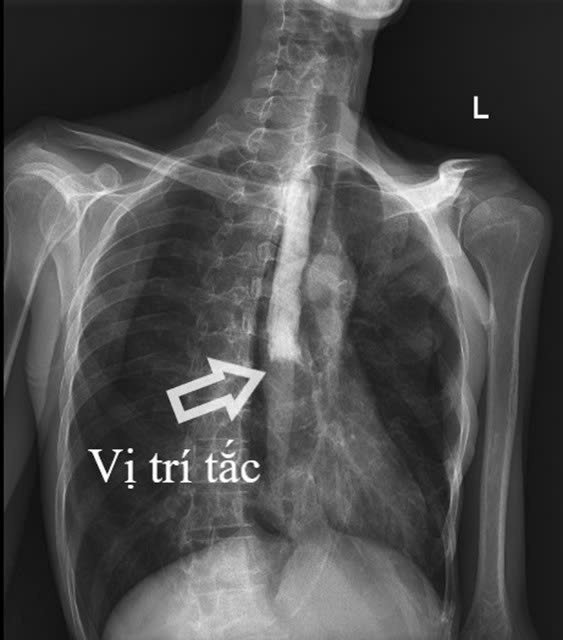

Kết quả cận lâm sàng cho thấy hình ảnh tắc thực quản hoàn toàn đoạn 1/3 giữa và viêm lan tỏa dạ dày, ruột non, viêm phúc mạc do thủng tạng rỗng.